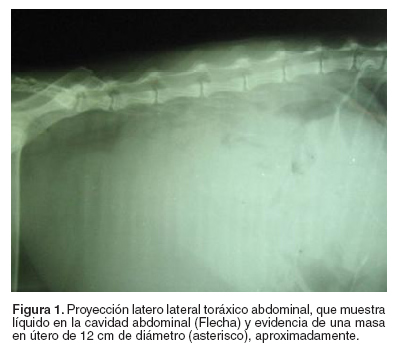

A la paciente se le realizó un hemograma que reportó una anemia normocítica normocrómica regenerativa, además de una neutrofilia absoluta (véase Tabla 1); el examen radiológico en proyección latero lateral y ventro dorsal de la cavidad abdominal y torácica, mostró gran cantidad de líquido en la cavidad abdominal y se pudo evidenciar una masa en el útero de aproximadamente 12 cm de diámetro (véase Figura 1). Al paciente se le realizó una abdominocentesis con la extracción de 70 ml del contenido serosanguinolento que no coaguló; en este líquido no se evidenció la presencia de células neoplásicas; además, se tomó muestra de orina mediante cistocentesis y el urianálisis indicó los parámetros normales.